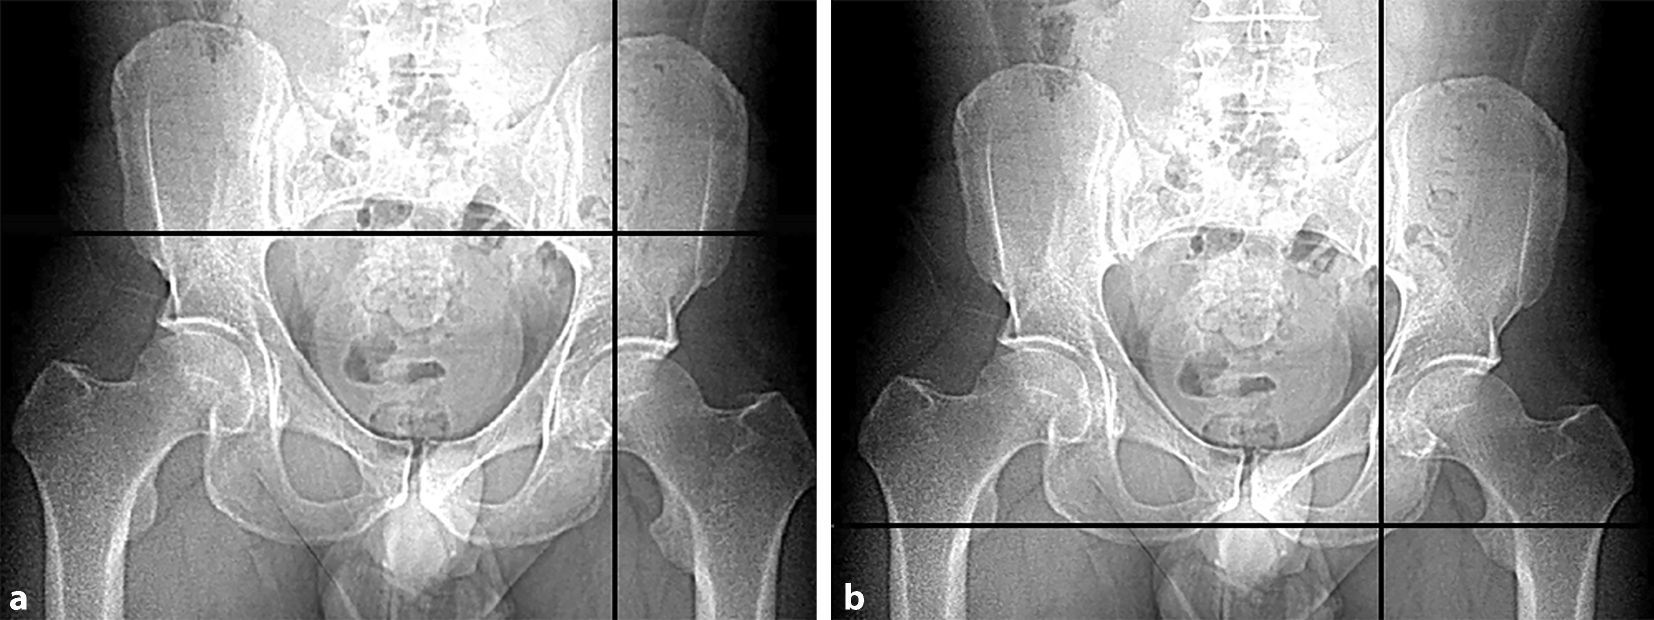

Fig. 1

a Injury mechanism of anterior column with posterior hemitransverse fractures (ACPHF). ACPHF typically result from force transmission via the greater trochanter and the femoral neck with the hip joint in extension. Due to the anteversion of the femoral neck the anterior column is affected first and frequently shows a multifragmentary fracture pattern. Further protrusion of the femoral head leads to a simple posterior hemitransverse fracture and a fracture component in the transition zone between the anterior column and the quadrilateral plate. The quadrilateral plate therefore remains in osseous continuity with the posterior column. These two fracture components allow for an internal rotation of the posterior column as a result of the medial protrusion of the femoral head. Accordingly, the quadrilateral plate is not separated from the two acetabular columns. It is internally rotated in osseous continuity with the posterior column. b Fracture components of ACPHF. The injury mechanism described in a results in the typical fracture patterns of ACPHF with the following fracture components and characteristics: multifragmentary or comminuted anterior column fracture; simple posterior hemitransverse fracture; internal rotation of the posterior column and the attached quadrilateral plate; impaction of the articular surface of the superomedial dome (“gull sign”). c “Gull sign”: impaction of the articular surface of the superomedial dome results from force transmission via the femoral head. The radiological appearance of this impaction has been described as “gull sign” referring to children’s style of drawing sea gulls. The “gull sign” is associated with a poor outcome after open reduction and internal fixation of acetabular fractures [1315]